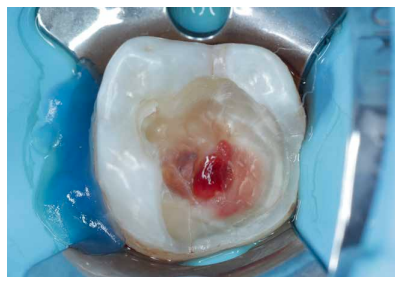

Se continuó con la remoción no selectiva de la caries y de la restauración previa con fresas redondas de turbina y contraángulo (Figura 3). Posteriormente, se expuso la pulpa en la zona más cercana a la lesión en una extensión de unos 2-3 mm con una fresa estéril redonda de diamante montada en turbina con abundante refrigeración. Se observó la pulpa y la sangre era roja brillante (Figura 4). Se controló el sangrado con una bolita de algodón embebida en hipoclorito de sodio 3% que se aplicó durante 2 minutos (Figura 5).